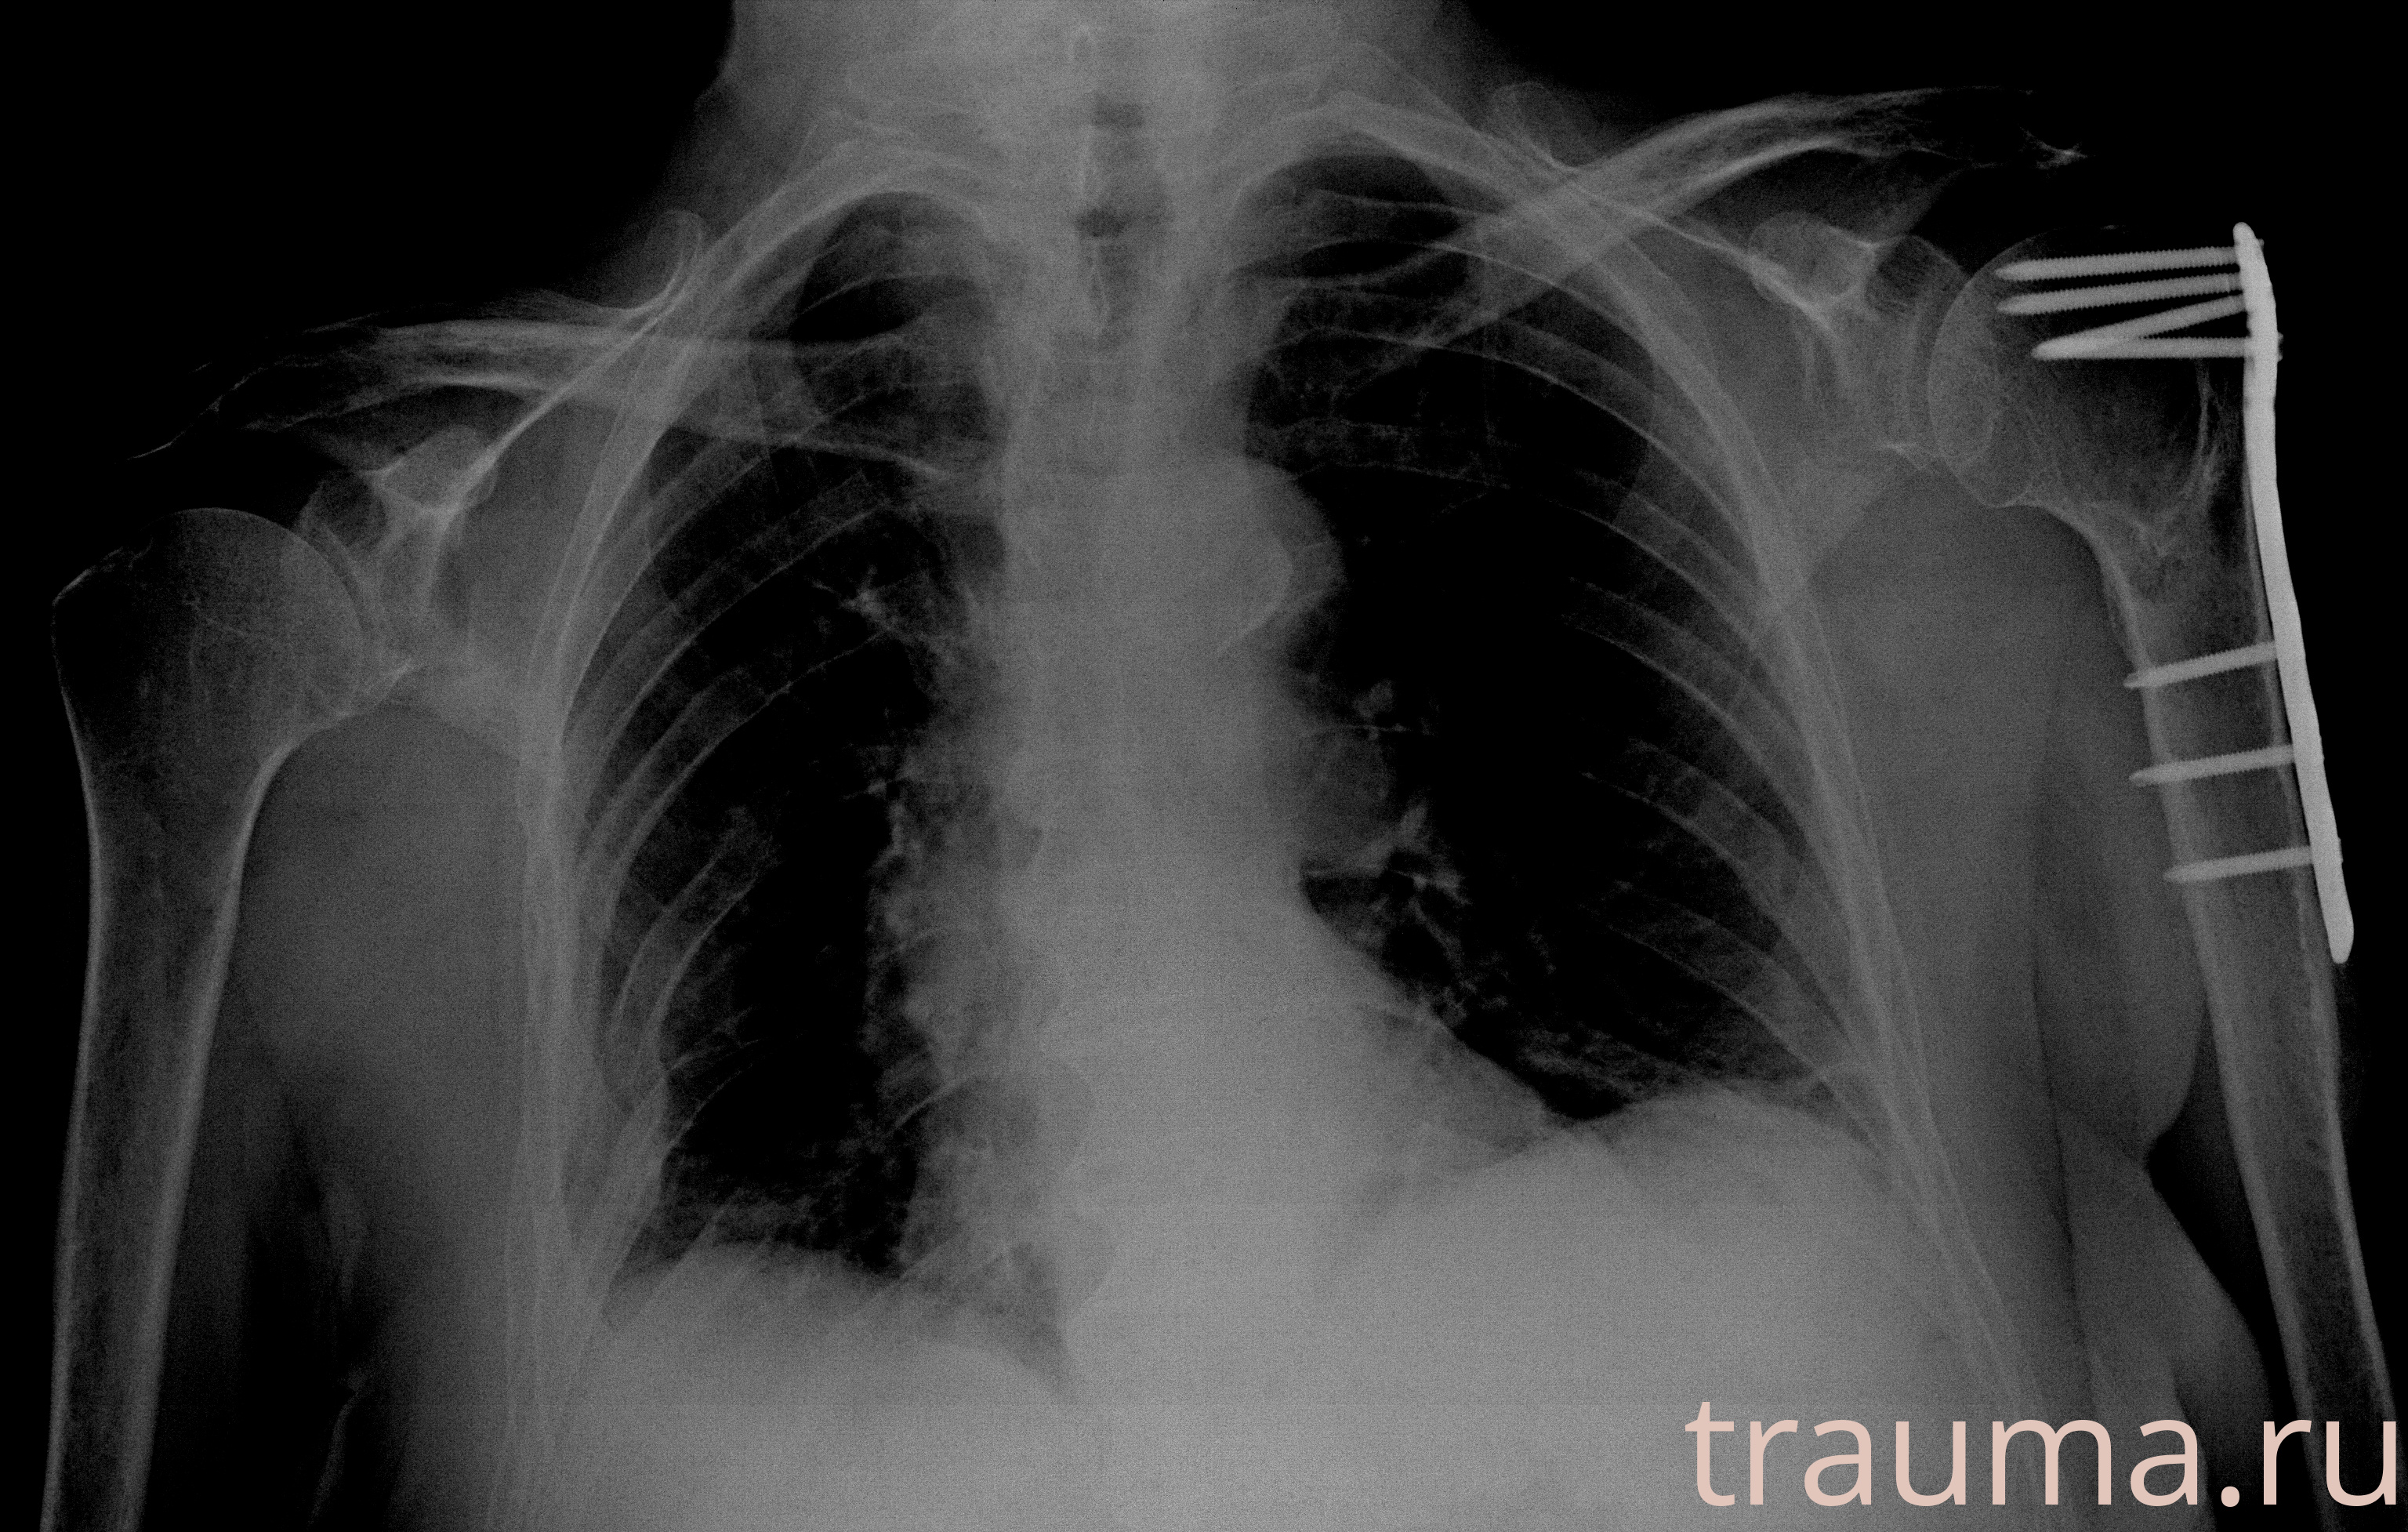

Рентген на дому: по вашему адресу приезжает врач-рентгенолог, травматолог-ортопед с мобильным рентгеновским аппаратом, проводит диагностику травмы или заболевания, делает необходимые рентгенограммы, дает рекомендации по дальнейшему лечению. Получить качественные снимки в домашних условиях возможно благодаря уникальной методике, разработанной МосРентген Центром для института  Склифосовского